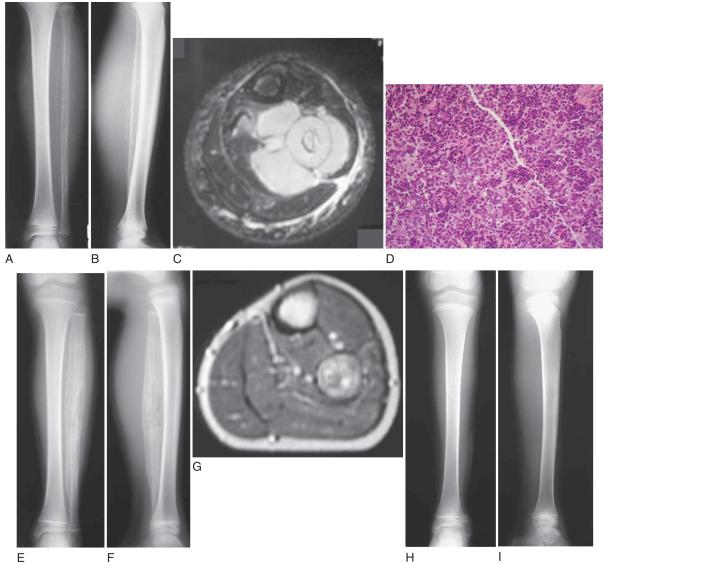

EWİNG SARKOM

Doktor Mehmet Subaşı

Kemiğin 4. Sıklıkta rastalana primer tümörüdür,ancak...